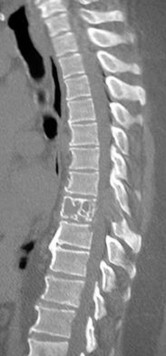

A 55-year-old diabetic male presents with severe mid-thoracic back pain, subjective fevers, and progressive bilateral leg weakness over the past 24 hours. His CRP is 120 mg/L.

An urgent MRI demonstrates a ventral spinal epidural abscess at T8-T10. Which of the following constitutes an absolute indication for urgent surgical decompression?